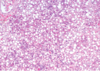

Enzymes Indicating Hepatocellular Damage

(4)

- these are the classic ones- leakage enzymes

- tell us there is damage to the hepatocytes

Hepatocellular damage - “leakage”

- these enzymes are readily available from the cytosol of the hepatocytes

- if there is damage to hepatocytes and it dies, the enzymes in hte cytoplasm will be released

- or some degree of damage to hepatocyte causes wall to release a little bit of cytoplasmic material

- blebosome: will have a bit of cytoplasmic material in it

- if you even just have a lot of blebbing from a large amount of hepatocytes, will still see an increase of these specific enzymes

Hepatocellular Enzymes: ALT and GLDH

- will increase about 12 hours after injury

- last for about 1-2 days

- more common in SA

large animals: ALT activity is very low!